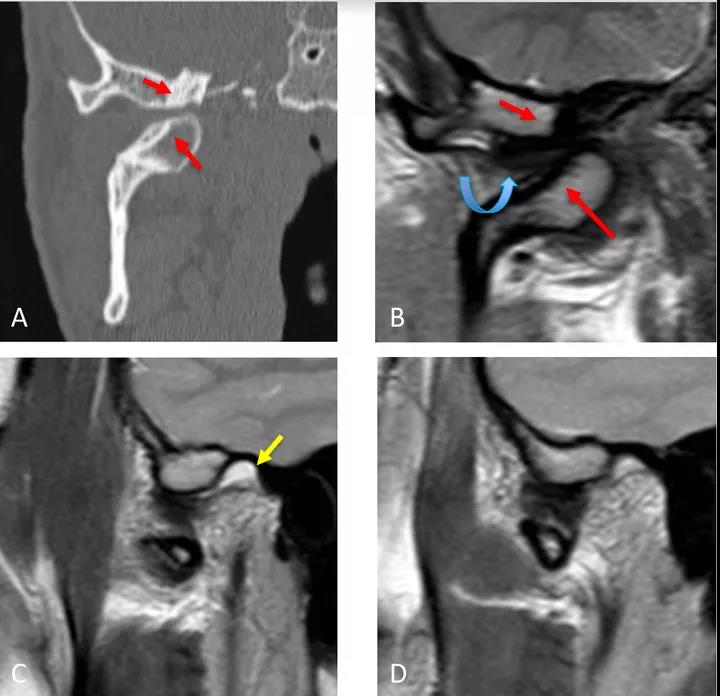

病例二:顳下頜關節(jié)脫位

冠狀面CT圖(A)和冠狀面PDWI圖(閉口)(B):顯示由于先前骨折導致的下頜髁突內(nèi)側移位的顳下頜關節(jié)脫位,與骨折畸形愈合、前上髁和后顳嵴硬化(紅色箭頭)相關。關節(jié)盤位于下頜骨髁突和顳突之間,失去正常的形態(tài)(彎曲箭頭)。

矢狀位T2WI圖(閉口)(C):顯示正常位置的下頜骨髁突及關節(jié)積液(黃色箭頭)。

矢狀位PDWI圖(開口)(D)顯示髁突明顯偏移。